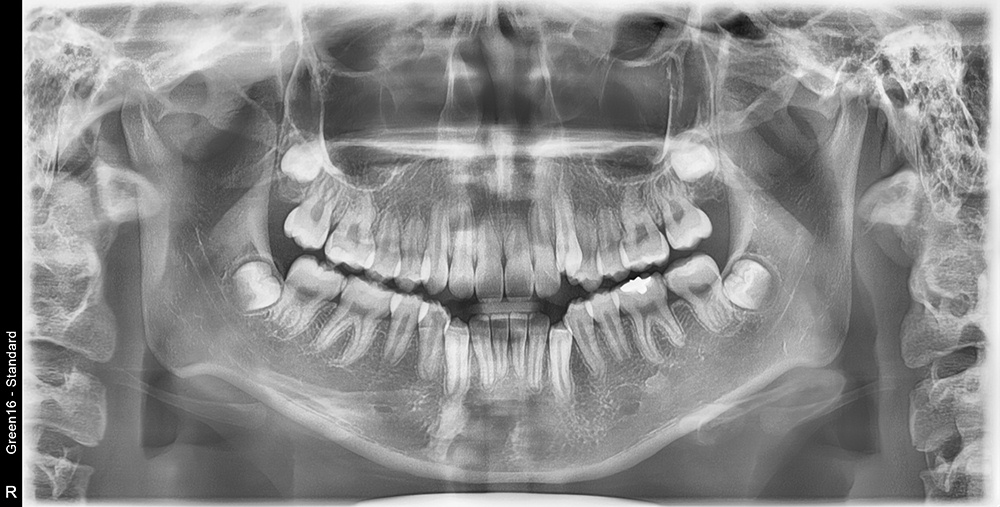

치료 전 사진입니다.